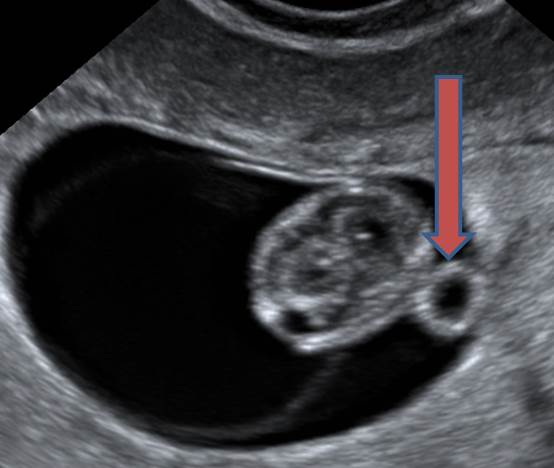

10 недель. Какая структура отмечена стрелкой?